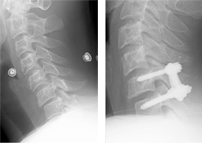

환축추 아탈구

환축추 아탈구 수술 전/후 X-ray

수술 전

수술 후